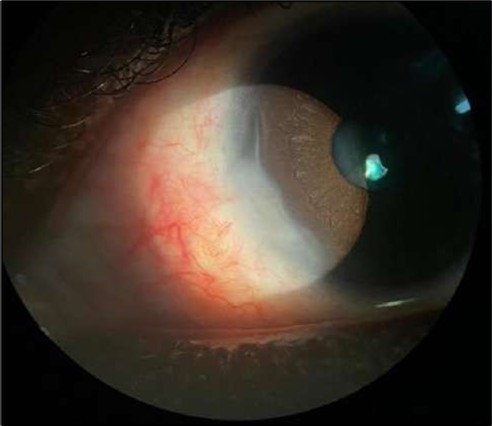

On the current presentation, Snellen VA was 6/6 in the right eye and 6/9 in the left eye, with normal IOP. The left eye demonstrated mild upper lid edema and intense nasal ciliary injection. Slit-lamp evaluation revealed a crescentic area of stromal corneal melting between 7 and 10 o’clock nasally, with overhanging edges and a fluorescein-positive base. No corneal infiltrates were present, and the surrounding stroma remained clear. The anterior chamber was deep and quiet, lens was transparent, pupil was round and reactive & normal posterior segment. Anterior segment optical coherence tomography (AS-OCT) confirmed a localized ulcer, measuring 1324 µm in horizontal width and extending to a depth of 380 μm, compared with an adjacent healthy corneal thickness of 824 µm, corresponding to approximately 46.1% stromal thinning (Figure 1a, Figure 1b, Figure 1c)

Figure 1a.Left eye (OS), on presentation. Slit-lamp image: crescent-shaped peripheral corneal ulceration located nasally, with severe adjacent conjunctival injection, peripheral thinning, and stromal infiltration.

Figure 2.OS, Slit-lamp image after a course of intravenous methylprednisolone therapy showing marked reduction in conjunctival hyperemia and stromal infiltration.